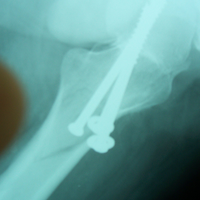

Case:7 Fracture Neck Femur with Implant failure and Re-Fixation with hemi-arthroplasty

Alcoholic Gardener by profession had slipped in bathroom & fell. He sustained fracture neck femur.He was operated with closed reduction & CC Screw fixation under IITV. Two weeks’ post fixation he again fell & sustained fracture in sub trochanteric region. He was treated with Hem-Arthroplasty with Tension band wiring.

Pre-Op

Post-Op

Post Fall